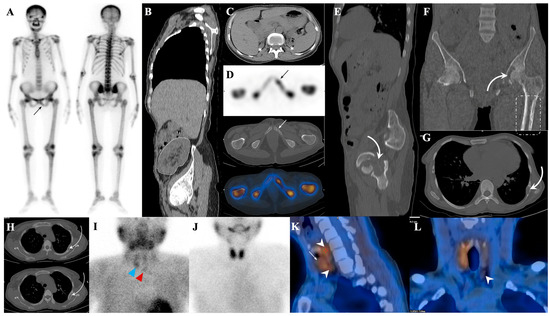

7.1. Metastatic Superscan

7.1.1. Superscan Pattern in Patients with Prostate Cancer

7.1.2. Dynamic Changes in Prostate Cancer Patients with Superscan

7.2. Metabolic Superscan

7.3. Distinguishing Metabolic Superscan from Metastatic Superscan